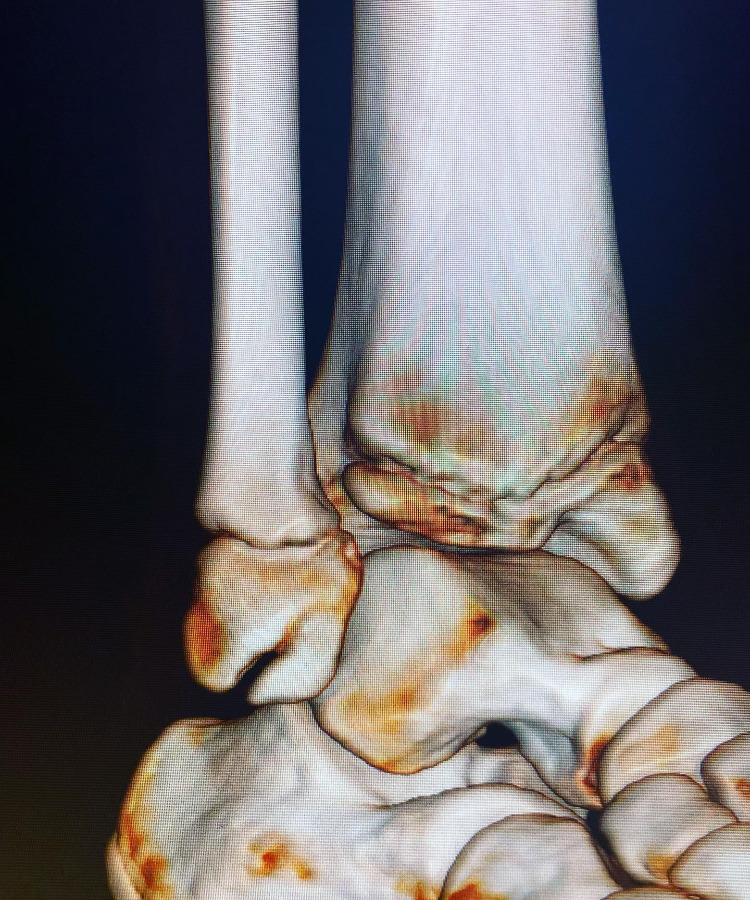

Pie / Rodillas en equino varo

El pie equinovaro es una deformidad congénita donde el pie está en punta y la planta girada hacia adentro.

Las deformidades de pie y rodilla incluyen genu varo, genu valgo, pie plano y pie cavo, con causas congénitas o postraumáticas.